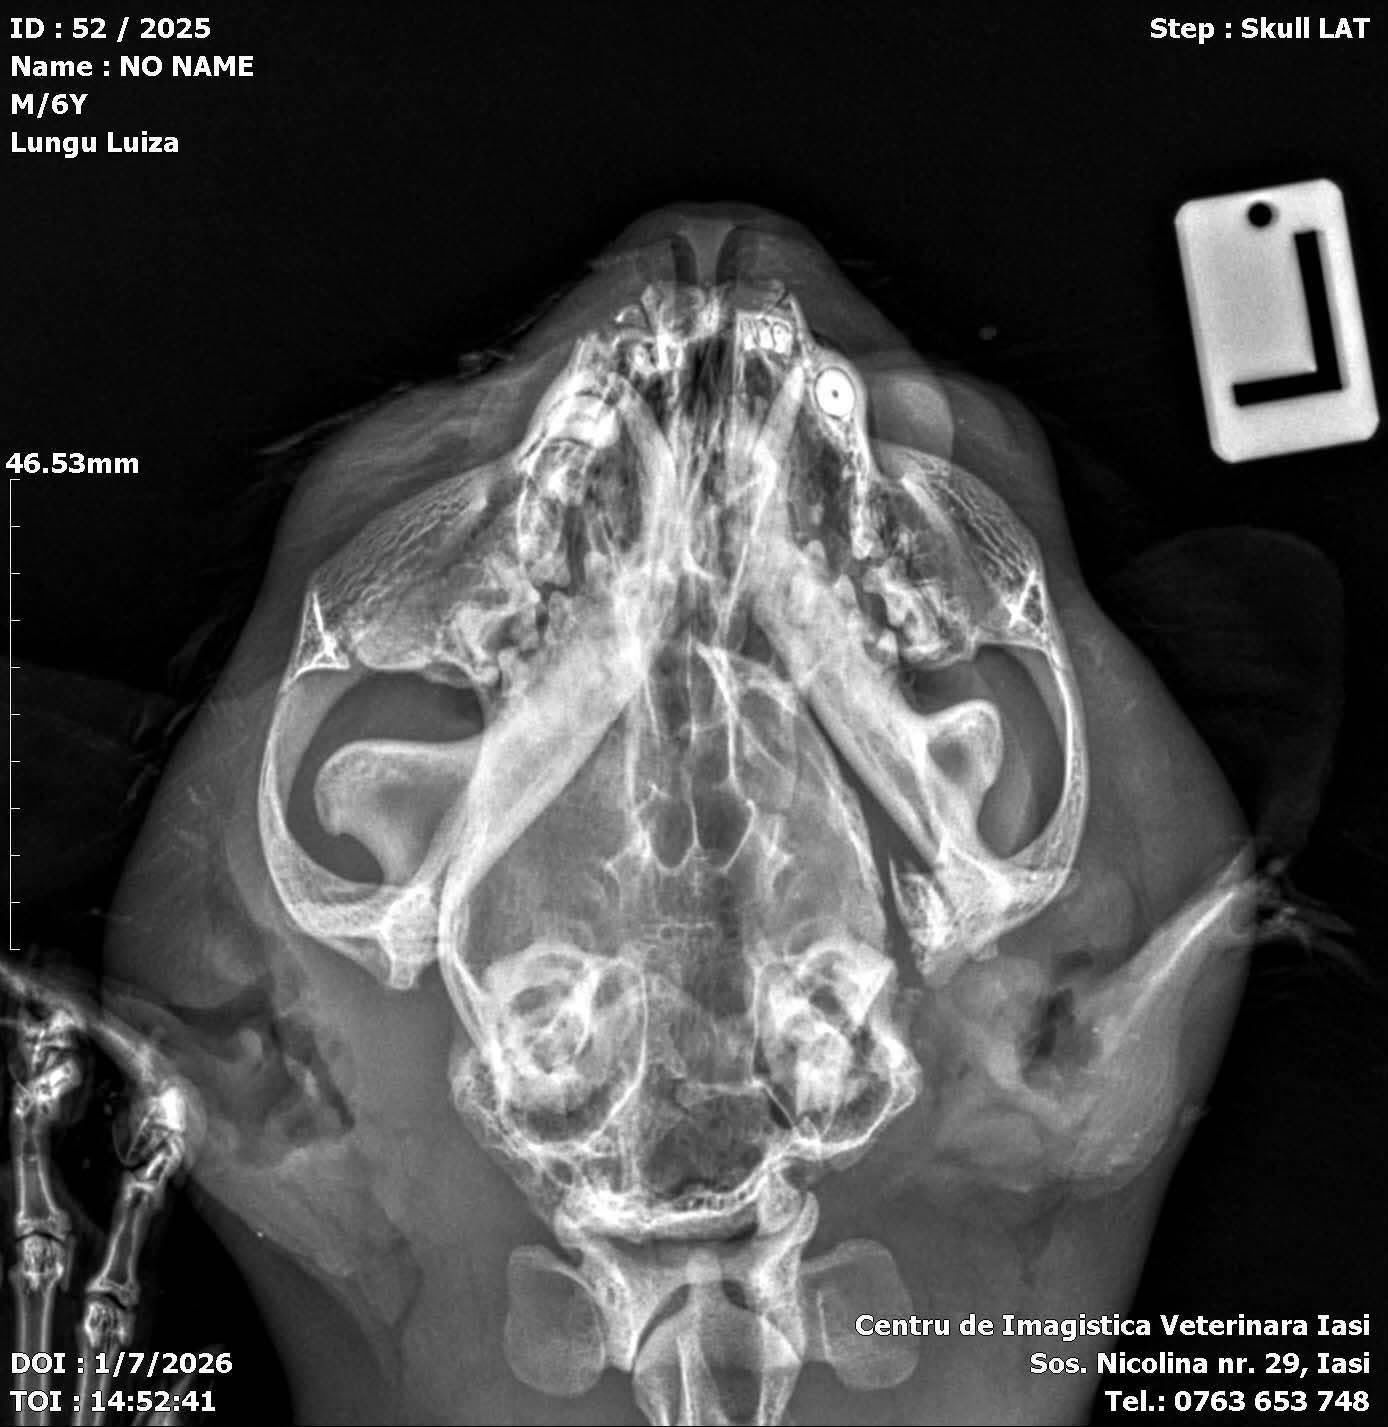

Beim Tierarzt wurde festgestellt, dass mein Unterkiefer an mehreren Stellen gebrochen war und auch mein Gaumen genäht werden musste. Eine lange Zeit voller Behandlungen, Geduld und Hoffnung begann. Zwei Monate lang kämpfte ich mich Schritt für Schritt zurück – bis ich schließlich wieder selbstständig fressen konnte.

Der Unfall hat jedoch eine Spur hinterlassen:

Ich habe mein Augenlicht fast vollständig verloren und sehe nur noch einzelne Schatten.